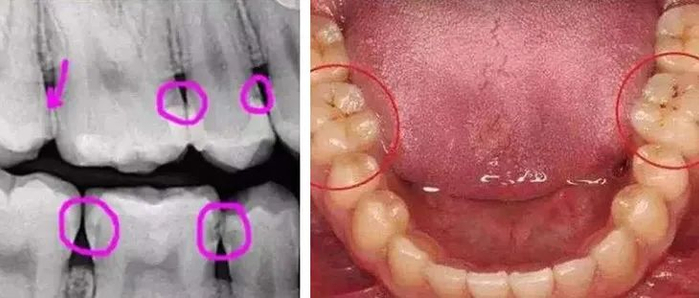

看到“牙片”的那一刻惊了,好几颗蛀牙,下排牙齿刷不干净,都是脏兮兮的牙结石

牙科朋友说,虽然现在不痛,但蛀牙会塞牙,时间久了成为牙洞,种牙麻烦大。